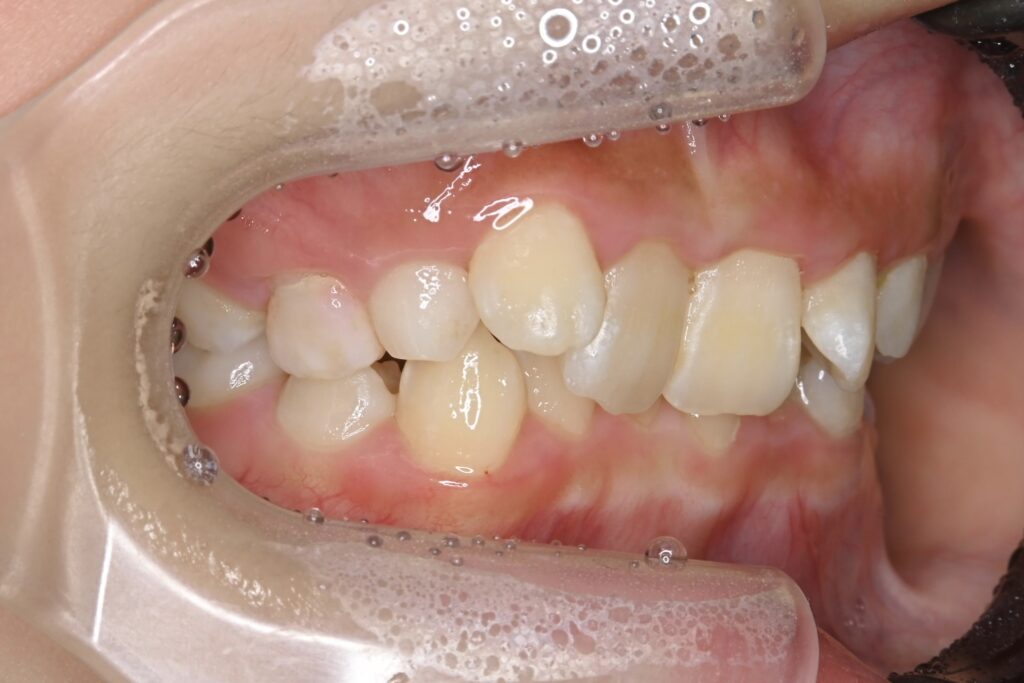

7歳 男児 小児矯正

AFTER

主訴 通っている歯医者で矯正した方がいいと言われて気になっている。下の前歯がでこぼこしている。

診断名・主な症状 下顎前歯の叢生を伴う過蓋咬合

治療内容 上下の歯並びの幅を拡げつつ、前歯の関係を改善しました。

使用装置 急速拡大装置

リンガルアーチ

機能的矯正装置(マイオブレース)

抜歯部位 抜歯なし

治療期間 2年 + 後戻り止め期間(3年 )

通院回数 20回

費用 50万円程度(税別)  29331

リスク・副作用 痛み、歯肉退縮、歯根吸収、抜歯に伴う出血や腫れが生じることがあります。